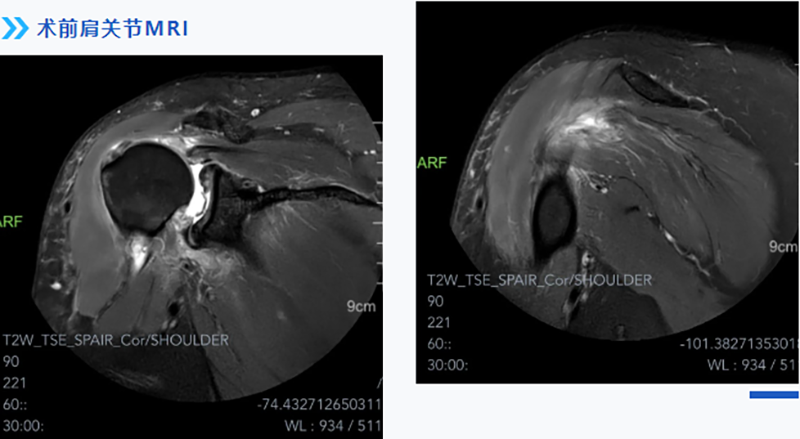

經(jīng)過(guò)多方打聽(tīng),張師傅慕名來(lái)到柳州市人民醫(yī)院運(yùn)動(dòng)醫(yī)學(xué)科就診。運(yùn)動(dòng)醫(yī)學(xué)科主任韋釗嵐博士結(jié)合患者實(shí)際情況,仔細(xì)查體及閱片后給出了明確診斷:巨大肩袖撕裂,腋神經(jīng)損傷(后上型巨大肩袖撕裂回縮導(dǎo)致神經(jīng)牽拉)。

醫(yī)生介紹,肩袖主要由岡上肌、岡下肌、肩胛下肌及小圓肌組成。巨大肩袖撕裂一般指撕裂直徑大于5cm或撕裂的范圍波及2根以上的肩袖。因?yàn)樗毫逊秶?,受累肌肉多,無(wú)論從手術(shù)方案制定還是手術(shù)技術(shù)難度上均是肩袖手術(shù)中最具挑戰(zhàn)的,特別是對(duì)多部分軟組織進(jìn)行組織松解和調(diào)節(jié)平衡。